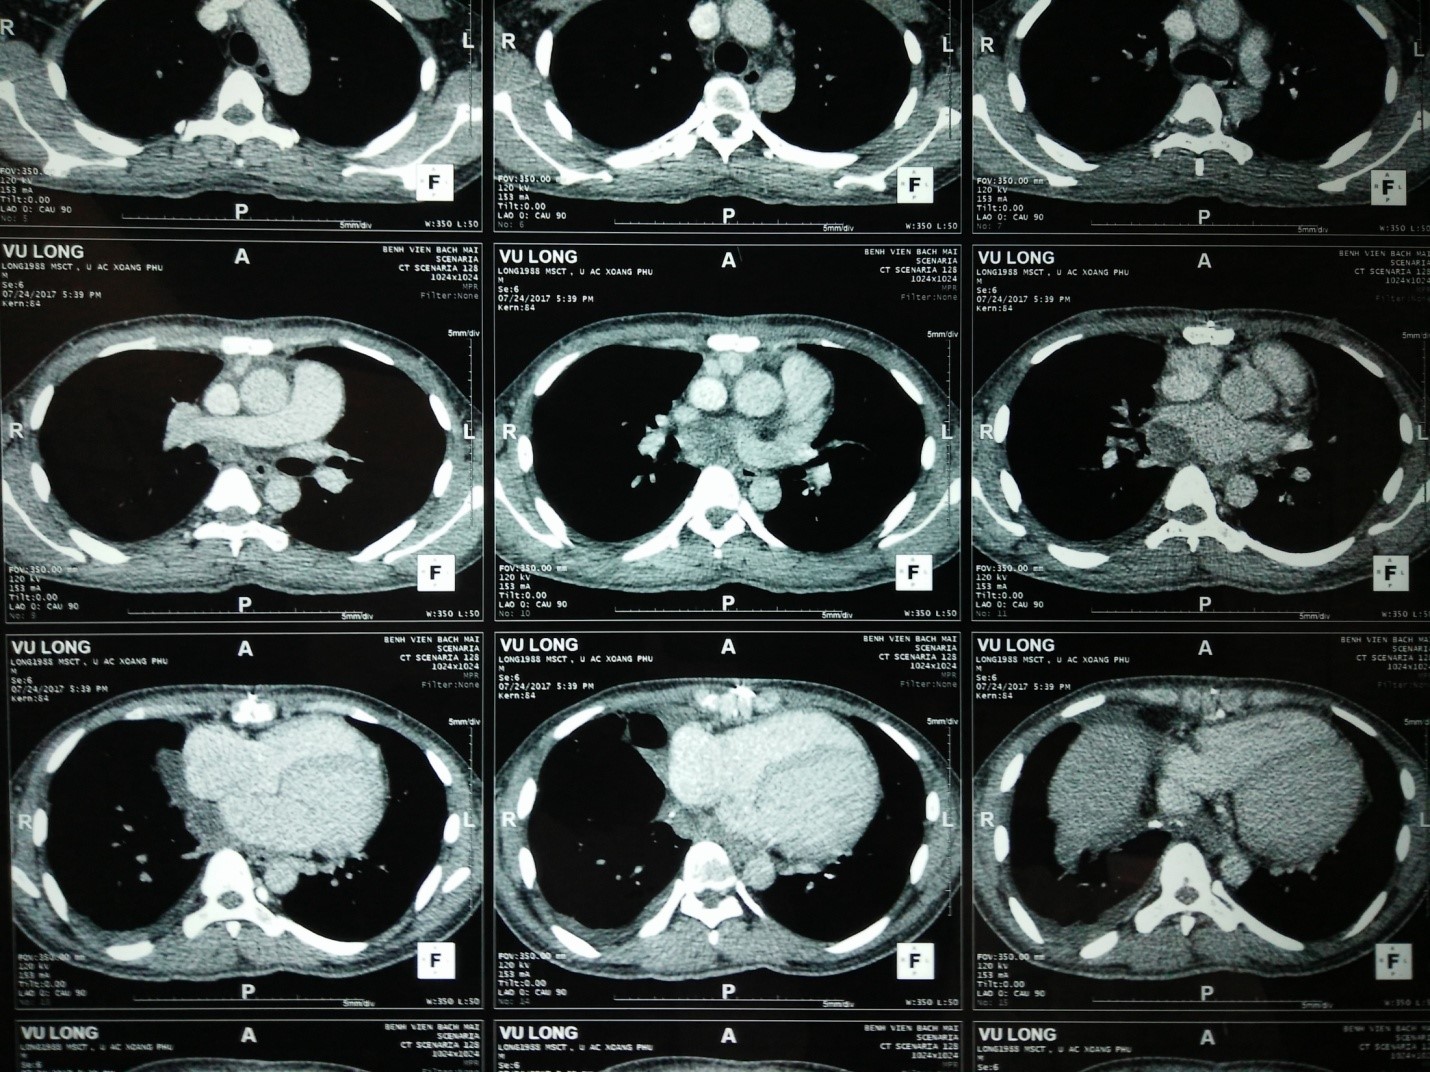

Hình 2: Hình ảnh chụp cắt lớp vi tính (CT) lồng ngực sau một chu kỳ điều trị hoá chất

Sau điều trị 1 đợt (sau 1 chu kỳ), kèm theo thuốc dự phòng hạ bạch cầu, bệnh nhân dung nạp và đáp ứng tốt, có một số tác dụng phụ như mệt, ăn kém, buồn nôn, rụng tóc.

Bệnh nhân tiếp tục được điều trị theo phác đồ AIM thêm 2 chu kỳ. Bệnh nhân vẫn dung nạp tốt, không có hạ bạch cầu, công thức máu và chức năng gan thận trong giới hạn bình thường.